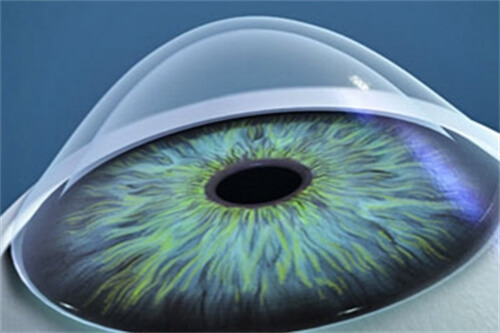

无衍射环设计:

传统多焦点晶体依赖衍射环分割光线,易产生光晕干扰;艾无极采用高阶渐进折射技术,光学区度数从周边向中央平滑递增,形成连续焦深,实现33厘米至无限远的平滑过渡。